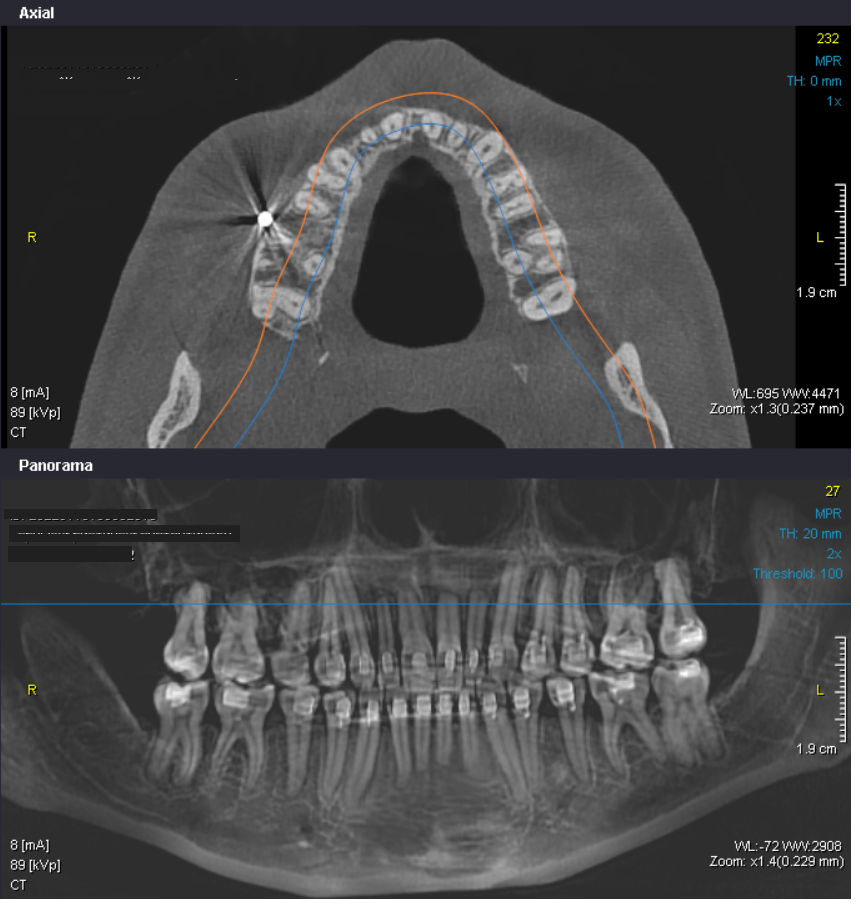

После брекетов я получила осложнения, который видны на КТ. Разместив снимки КТ в ИИ, тот настоятельно мне порекомендовал нарастить костную ткань, однако, обратившись к пародонтологу я узнала, что к своим родным зубам нарастить костную ткань нельзя, особенно в районе резцов и мне предложили только закрытие рецессий, когда они появятся. В связи с чем, я хотела бы обратиться за помощью, помогите пожалуйста разобраться в моих снимках и понять, как правильно действовать в данной ситуации, чтобы сохранить свои родные зубы как можно дольше. Буду благодарна за профессиональное мнение и рекомендации. (Фотография зерькальная)